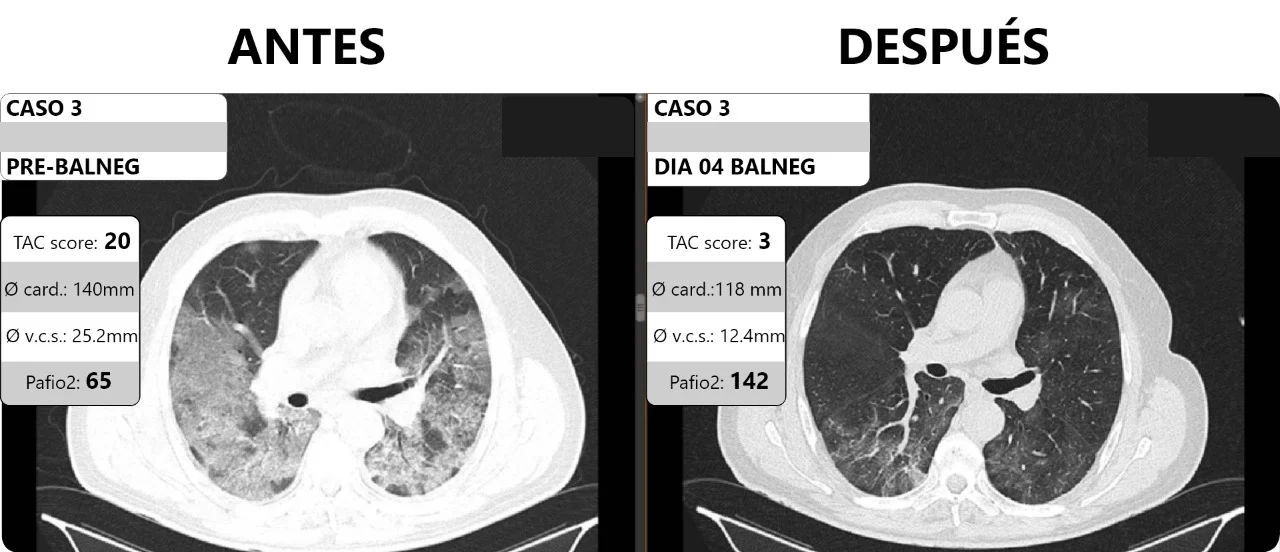

El estudio, describe el tratamiento aplicado a una serie de 20 pacientes con Covid-19, que presentaban edema pulmonar y determinadas características clínicas, en los que se empleó una estrategia terapéutica diferente a la convencional, obteniendo excelentes resultados. Dicha estrategia se basa en la administración médica de un diurético, furosemida, junto con una terapia de restricción hídrica dirigida a lograr una condición que se denomina “balance negativo de fluidos”.

Pero al equipo médico no le convencía esa interpretación. En junio, un paciente internado en la clínica ayudó a cambiar la perspectiva, pasando de tratar una supuesta neumonía a un edema pulmonar: «Tenía una neumonía de evolución muy rara. Prestamos atención a algunos datos llamativos, como el eje cardíaco, el diámetro de la vena cava superior que analizamos en conjunto con el Equipo de Imágenes; pensábamos que tenía una falla cardíaca, pero experimentados cardiólogos vieron el caso. El corazón estaba en perfecto estado. Dado que había evidencias tomografías de edema pulmonar, se lo trató en consecuencia, como un edema de pulmón de origen incierto. Es que claramente se veían signos en la tomografía de un edema pulmonar».

Mientras a una neumonía con tormenta de citoquinas se la trata con antiinflamatorios, a un edema se lo trata en cambio con diuréticos. Con ese cambio de óptica, el paciente «Mejoró rápidamente y al efectuarse una tomografía de control se pudo evidenciar una resolución rápida y significativa, lo cual era sorprendente puesto que el COVID nunca mejoraba de esa manera, no obstante, en este caso sí».

Pusieron a prueba la hipótesis e hicieron un «tratamiento diurético muy estricto a varios pacientes» con COVID en grave estado, con distintos factores de riesgo, algunos vacunados, otros no. «Vimos respuestas muy buenas en el 100% de los casos», aseguró Santos. El tratamiento duró relativamente pocos días, entre 4 y 8, dependiendo del paciente.